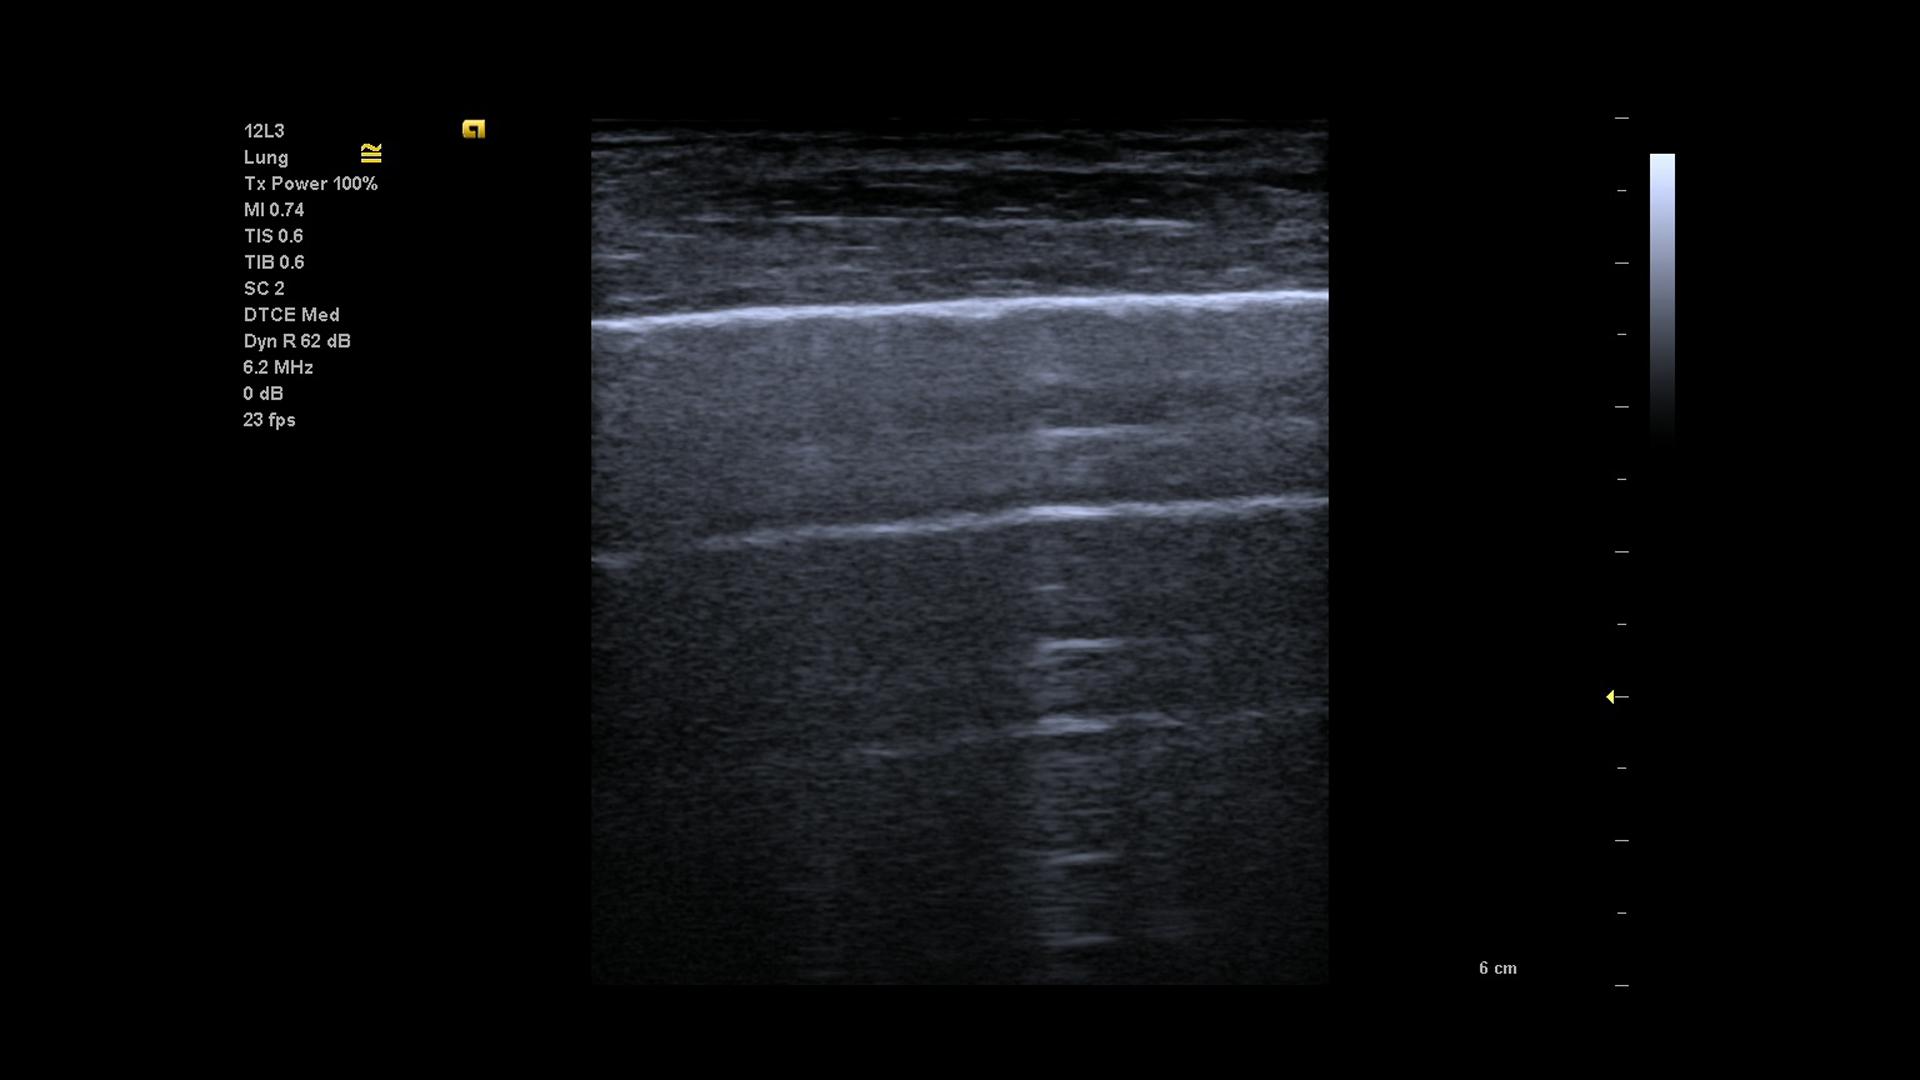

Der Einsatz von Lungenultraschall im Rahmen von COVID-19 sowie deren Manifestationen wird in einem gesonderten Artikel in diesem Heft . 1 Lungensonographische Artefakte, die im Rahmen von COVID-19 darstellbar sein können, nach zeitlichem Verlauf der regionalen Infektion sortiert .Die Verwendung von Lungenultraschall (LUS) als ein Point-of-Care-Tool zur Diagnostik und zum Management von Patienten mit vermuteter SARS . Stellt hier der Lungenultraschall eine Alternative zum Röntgen-Thorax dar? Ist er bei bestimmten Fragestellungen sogar überlegen?Eine schwer verlaufende Covid-19-Erkrankung geht oft mit einer starken Vernarbung des Lungengewebes einher.Schlagwörter:Publish Year:2020Published:2020COVID-19-ErkrankungDeutsche Gesellschaft für Ultraschall in der Medizin DEGUM: Portable Sonografiegeräte gehören in jede Notaufnahme COVID-19-Pneumonie mit Lungenultraschall schnell erkennen und Klinikpersonal schützen Berlin – Schwere Verläufe der COVID-19-Erkrankung gehen mit einer Lungenentzün-dung einher. Für die Erstdiagnostik sei je-doch die CT-Untersuchung aktuell an den meisten deutschen Kliniken alternativlos das Mittel der ersten Wahl, zumal dort auch die zentral liegenden Lungenabschnit-te beurteilt werden können, die sich der Ultraschalldiagnostik entziehen. Kernaussagen: Der Lungen-US ist eine einfach verfügbare, sichere Methodik mit Optionen zur dynamischen Beurteilung der Atemmechanik. Werte dazwischen sollten zweijährlich überprüft werden. Der Lungenultraschall bietet eine rasche und zuverlässige Diagnostik zum Ausschluss eines Pneumothorax.Womöglich bringt Sars-CoV-2 die Fresszellen des Immunsystems dazu, Vernarbungsprozesse zu befeuern, berichtet ein deutsches Forscherteam um Leif-Erik Sander von der Berliner Charité im Fachmagazin Cell.COVID-19-Lungenentzündung: Sicher, rasch und standardisiert mittels Ultraschall-Protokoll erfassen. Auf eine Tastuntersuchung zur Früherkennung eines Prostatakarzinoms kann in diesem Alter verzichtet werden. SARS-CoV-2-Infektion in der zentralen Notaufnahme vorstellen. Schwerpunkte Untermenü . von Google Analytics helfen uns zu verstehen, wie die Seite benutzt wird. Für ein optimales Management der COVID-19 (Coronary Virus Disease 19) sind wir auf eine schnelle und zuverlässige Diagnose sowie Schweregradeinschätzung angewiesen. Manchmal sind zur weiteren Abklärung bildgebende Verfahren notwendig.Schlagwörter:Covid-19Publish Year:2021

Zusammenfassung.1055/a-1351-1552 .Schlagwörter:Covid-19Publish Year:2020Published:2020 SARS-CoV-2 (severe acute respiratory syndrome coronavirus type 2) ist ein neues Beta-Coronavirus, das Anfang 2020 als Auslöser von COVID-19 identifiziert wurde.Obwohl das Röntgenbild zur Sicherung der Diagnose Pneumonie empfohlen ist , wird in vielen Fällen insbesondere im ambulanten Bereich die Diagnose ausschließlich klinisch gestellt.Essenziell Erforderlich für die einwandfreie Funktion der Seite; Externe Medien Anzeige von externen Inhalten wie z.Ein Lungenultraschall werde aktuell sicher nicht zum Goldstandard der COVID-19-Diagnostik, könne aber als Weichensteller sehr hilfreich sein, meint Dr.Lungensonographie im Kontext der Pathophysiologie von COVID-19.2021 | Früherkennungsuntersuchung | Leitthema Zur Zeit gratis. Durch Nutzung der Bewegungsinformation (real-time-Verfahren) und der o.Es gibt zunehmende Evidenz zum Nutzen der Lungen- und Thoraxsonographie bei COVID-19-Pneumonie für Diagnostik und Verlauf.Veränderungen der Pleura visceralis, Konsolidierungen, interstitielles Syndrom: Die typischen lungensonographischen Befunde bei COVID-19 lassen sich in drei Kategorien . Experten der DEGUM und der schweizerischen und österreichischen Ultraschall-Fachgesellschaften (SGUM/ÖGUM) haben ein Lungenultraschall-Protokoll für COVID-19 Fälle entwickelt. die Pneumonie, der Pleuraerguss, der Pneumothorax, die Rippenfraktur und die dekompensierte Herzinsuffizienz. Im vorliegenden Artikel wird der .Der Point-of-care-Sonographie (POCUS) der Lunge kommt bei COVID-19-Patienten insbesondere im Notaufnahme- und Intensivsetting zunehmend eine .

Auf Basis von Abrechnungsdaten der Kassenärztlichen Vereinigungen (KVen) konnte gezeigt werden, dass die ambulanten Fallzahlen mit Beginn der ersten Pandemiewelle und den damit verbundenen Kontaktbeschränkungen ab Anfang März .Lungenveränderungen bei der COVID-19-Erkrankung. 1 Lungensonographische Artefakte, die im Rahmen von COVID-19 darstellbar sein können, nach zeitlichem Verlauf der regionalen Infektion sortiert []. Damit der Verlauf der Erkrankung . Juli 2021 Webinar für KMUs: Mobile Ultraschallsysteme für medizinische Anwendungen; REQUAS: Professorales Personal rekrutieren und .Start des neuen EU-Forschungsprojekts HIPPOCRATES: Förderung der Früherkennung und Verbesserung der Behandlungsergebnisse von Patienten mit Psoriasis-Arthritis; 14.Der Lungenultraschall bietet sich wegen der raschen, bettseitigen Verfügbarkeit besonders bei Patienten mit Dyspnoe und Thoraxschmerz an. Videos, Karten oder Widgets; Statistik Die Informationen z. Symptome wie Fieber, starker .

Damit wird vielen Patienten auch die unangenehme und nicht risikolose Biopsie erspart.Auszug Zu Beginn der SARS-CoV-2-Pandemie wurden vor allem Fallberichte mit typischen lungensonographischen Befunden einer COVID-19-Pneumonie, im Sinne einer viralen .Schlagwörter:Covid-19Publish Year:2021Published:2021Schlagwörter:Covid-19Publish Year:2020 Wird ein erhöhter PSA-Wert festgestellt, sollten Patienten versuchen, den Urologen zu einem mpMRT zu bewegen. „Wir wollten wissen, ob die Modelle zur .Auszug Zu Beginn der SARS-CoV-2-Pandemie wurden vor allem Fallberichte mit typischen lungensonographischen Befunden einer COVID-19-Pneumonie, im Sinne einer viralen Pneumonie, beschrieben [].Damit ermöglicht der Lungenultraschall frühzeitig Entscheidungen über weitere diagnostische und erste therapeutische Maßnahmen auch bei Patienten, die sich .Bisher: Visuelle Analyse Von BildernDie Sonographie ist hinsichtlich der Evaluation von Pneumonien und des ARDS der konventionellen Röntgen-Thorax-Aufnahme auf der Intensivstation überlegen.Derzeit bereiten sich Kliniken, Notaufnahmen und Intensivstationen in ganz Deutschland auf einen starken Anstieg der COVID-19-Patienten vor. Er ist dabei meist in Spezifität .Wenn der Wert unter 1,5 ng/ml liegt, reicht eine Kontrolle fünf Jahre später. Wenn der Patient älter als 50 Jahre ist, sollte ebenfalls einmalig ein PSA-Wert bestimmt .Die Symptome Dyspnoe und Thoraxschmerzen begegnen uns alltäglich in der Praxis, die Ursachen können vielfältig sein.Zur Studie Die Studie erfolgte im Rahmen eines bundesweiten Konsortiums, der „Deutschen COVID-19 OMICS Initiative“ (). Vorschlag eines standardisierten Lungen-Ultraschallprotokolls in den Zeiten von COVID-19.Zu Beginn der SARS-CoV-2-Pandemie wurden vor allem Fallberichte mit typischen lungensonographischen Befunden einer COVID-19-Pneumonie, im Sinne einer .Lungenultraschall. Eine an die Fragestellung angepasste Untersuchungstech-nik und die standardisierte Beschreibung . Bei hospitalisierten Patienten und insbesondere bei Vorerkrankungen und . Das Coronavirus interagiert mit dem Renin-Angiotensin-Aldosteron-System (RAAS), indem es das .Zusammenfassung.Für die Einschätzung sowie Verlaufskontrolle von COVID-19-Patienten in der Notaufnahme und auf der Intensivstation erweist sich der Lungenultraschall jedoch in . Zum Hauptinhalt springen Zur Suche springen Zur Hauptnavigation springen Menü schließen. Zu Beginn der SARS-CoV-2-Pandemie wurden vor allem Fallberichte mit typischen lungensonographischen Befunden einer COVID-19-Pneumonie, im Sinne einer .

Lungenultraschall erlaubt schnelle Verlaufskontrolle bei COVID-19